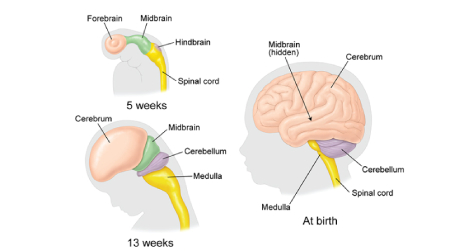

۱. رشد مغز نوزاد: یک فرآیند پیچیده و سریع

رشد مغز نوزاد از آغاز بارداری، یعنی از لحظه باروری، شروع میشود. در اوایل بارداری، سلولهای عصبی (نورونها) به سرعت تقسیم شده و در مراحل بعدی شروع به اتصال به یکدیگر میکنند. در این زمان، مغز نوزاد هنوز به اندازه یک دانه برنج است، اما شروع به ایجاد مسیرهای عصبی میکند که بعدها به مهارتهای مختلف مانند حرکت، زبان، و حافظه تبدیل خواهند شد.

در سه ماهه اول بارداری:

ساختار مغز در حال شکلگیری است و شروع به تشکیل قسمتهای مختلف خود میکند.

نورونها به سرعت در حال تقسیم و تشکیل اتصالات عصبی هستند.

در این مرحله، مغز نوزاد به طور کلی هنوز نمیتواند عملکردهای پیچیدهای انجام دهد، اما یک سری فعالیتهای ساده مانند حرکتهای ابتدایی عضلانی آغاز میشود.

در سه ماهه دوم بارداری:

مغز نوزاد شروع به فعالیتهای پیچیدهتری میکند. سیستم عصبی به شدت در حال گسترش است و این دوره یکی از مهمترین مراحل رشد مغز محسوب میشود.

در این مرحله، نوزاد قادر به انجام حرکتهای ابتدایی مانند تکان دادن دستها و پاها است.

سیستم شنوایی نوزاد در حال تکامل است و او شروع به شنیدن صداها از محیط اطراف، از جمله صدای ضربان قلب مادر و صدای محیط بیرونی، میکند.

در سه ماهه سوم بارداری:

مغز نوزاد به سرعت در حال رشد و تکامل است. در این دوره، بخشهایی از مغز که مسئول مهارتهای حرکتی، حافظه، و احساسات هستند، فعالیت بیشتری از خود نشان میدهند.

نوزاد شروع به واکنش نشان دادن به محرکهای بیرونی مانند نور و صدا میکند.

نوزاد قادر است چشمان خود را باز و بسته کند، به اطراف حرکت کند و در برخی موارد حتی مکیدن را آغاز کند.